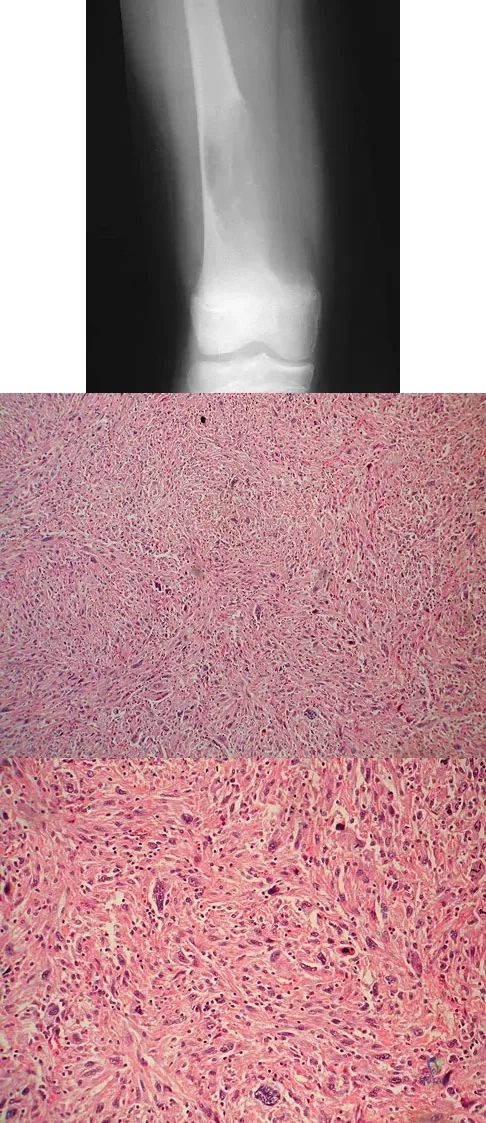

A 12-year-old girl has had increasing left knee pain for the past 3 months. A radiograph is shown in Figure 75a, and low- and high-power photomicrographs are shown in Figures 75b and 75c. What is the most appropriate treatment?

Explanation